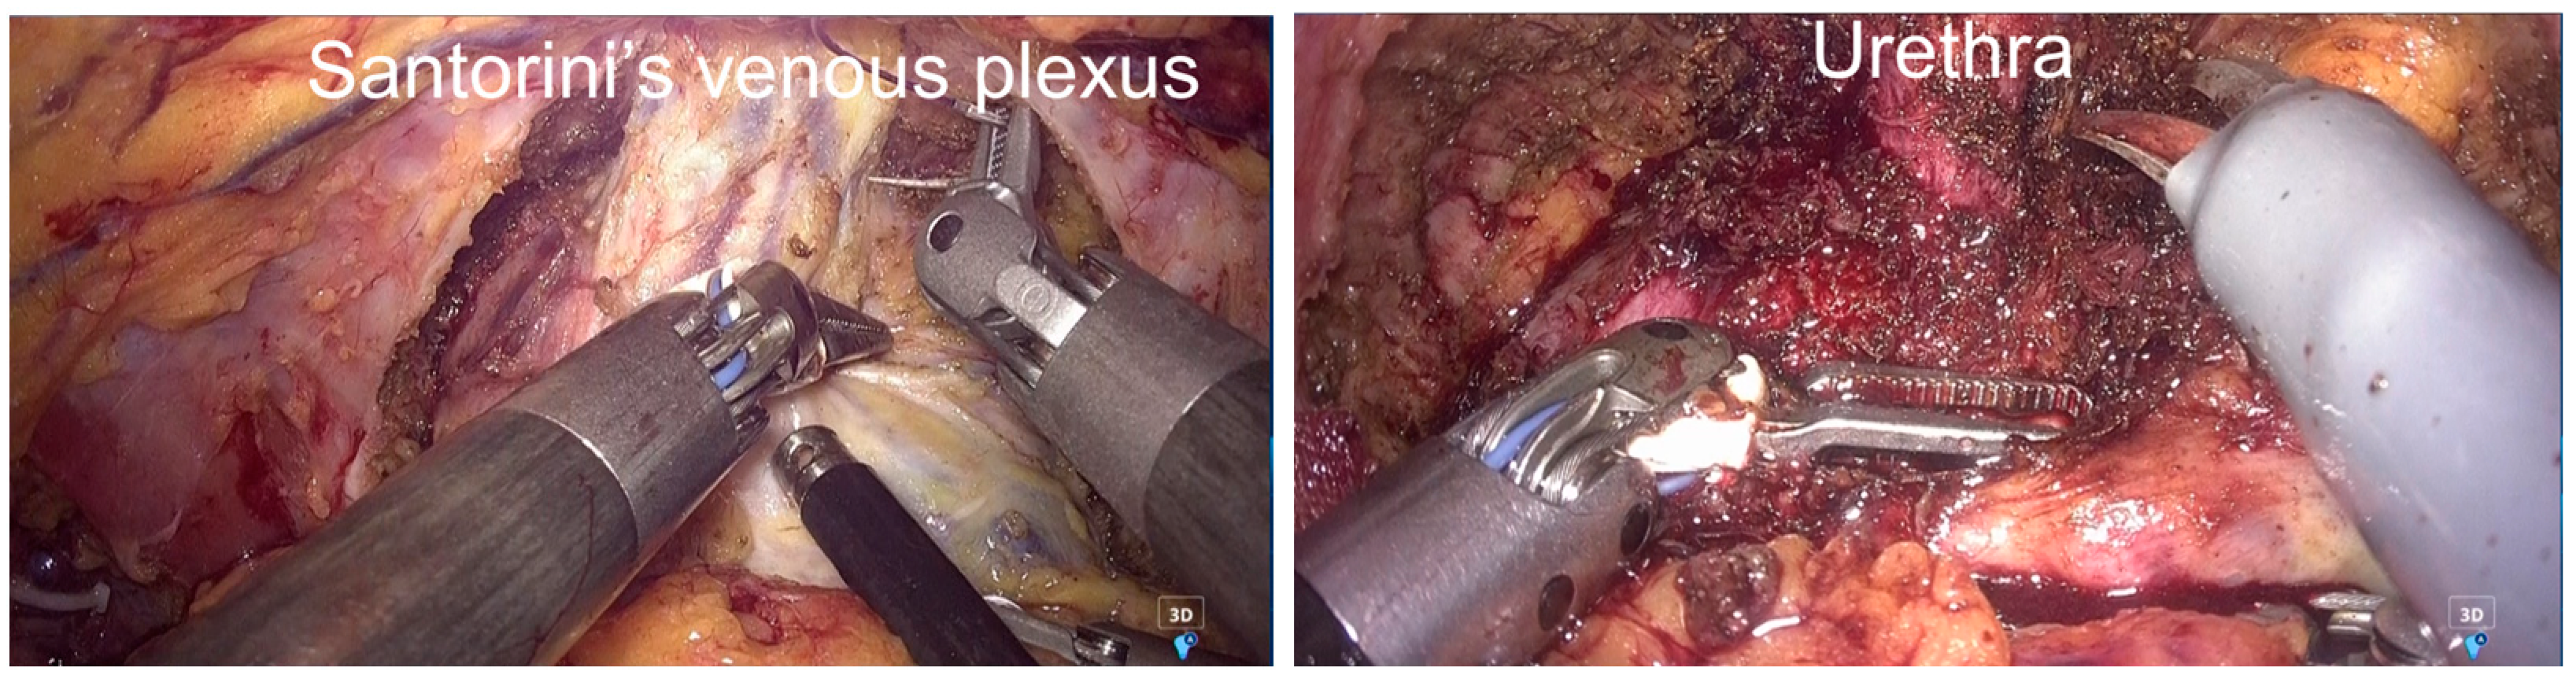

2.3. Surgical Procedure